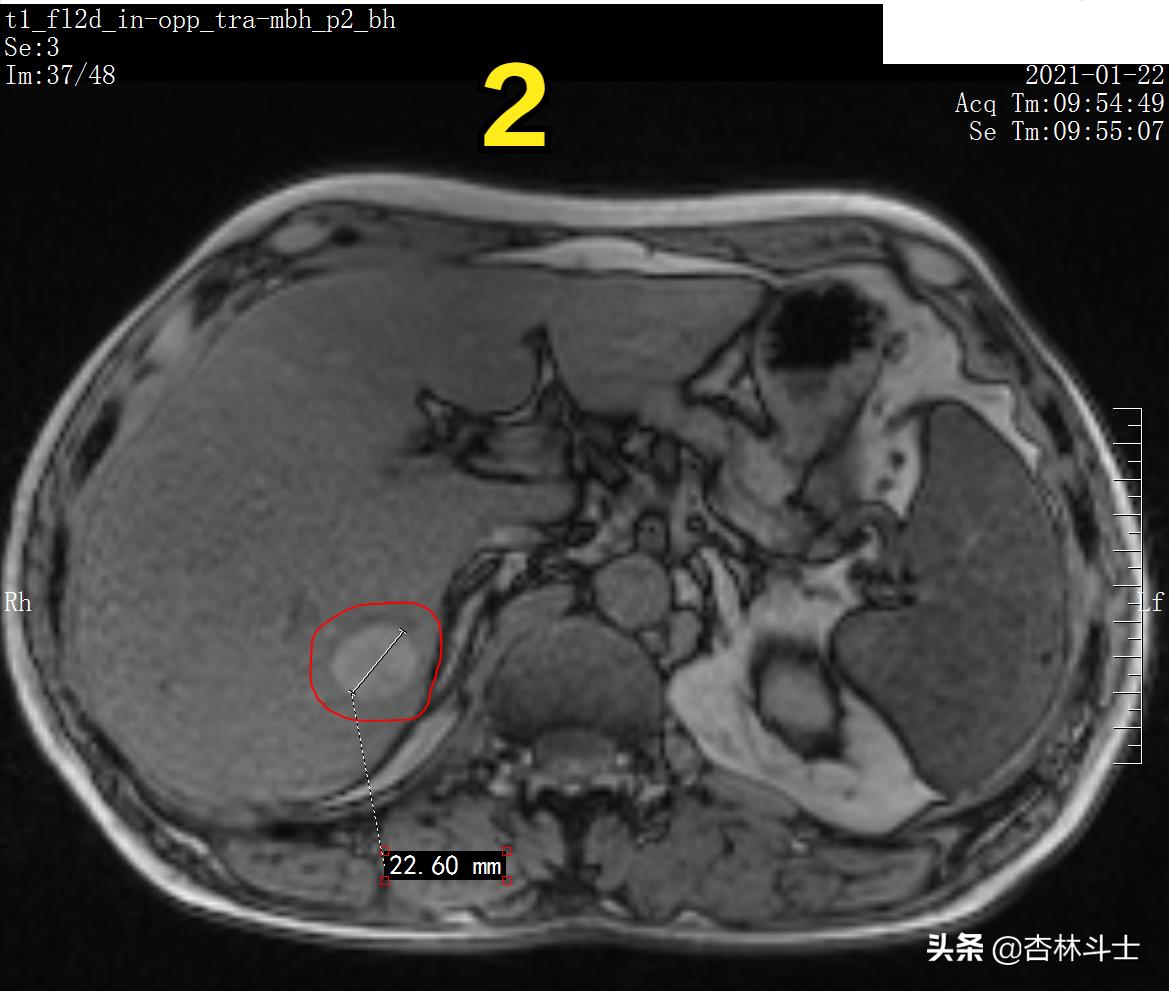

图2 T1加权像反相位

图2 T1加权像反相位上,病灶未见明显信号减低。病灶直径约22.6㎜